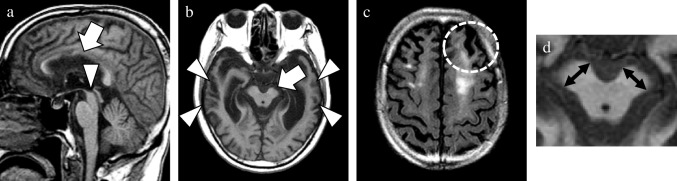

As the main neuropathology of more than half of the patients in the CBD mimics group was PSP, this group was further categorized into PSP-CBS and non-PSP-CBS subgroups. The MRI findings in the CBD and two CBD mimics subgroups are shown in Table 2. Compared with the PSP-CBS subgroup, the CBD group tended to show a higher SWMH ratio (56% vs 0%; p = 0.060). In the CBD group, SWMH was exclusively distributed in the frontal or parietal lobe at high convexity. Its sensitivity, specificity and accuracy to diagnose CBD were 56%, 86%, and 69%, respectively. Compared with the non-PSP-CBS subgroup, the CBD subgroup displayed relatively lower temporal GCA score and degree of asymmetry in the temporal and occipital lobes (0.5 [0.3–1.0] versus 1.5 [1.0–2.3], 0.0 [0.0–0.5] versus 1.0 [0.0–1.5], and 0.0 [0.0–0.0] versus 0.0 [0.0–0.0]; p = 0.073, p = 0.073 and p = 0.082, respectively). Confusable SWMH was detected in one patient with FTLD-TDP and one with GGT. Among the CBD mimics subgroups, the non-PSP-CBS subgroup showed higher frontal, temporal, and occipital lobe GCA scores (1.5 [1.0–2.5] versus 0.5 [0.5–1.0], 1.5 [1.0–2.3] versus 0.0 [0.0–0.5], and 0.5 [0.0–1.0] versus 0.0 [0.0–0.0]; p = 0.043, p = 0.011, and p = 0.019, respectively). By contrast, the degree of midbrain atrophy was most severe in the PSP-CBS subgroup (2.0 [1.0–2.0] versus 0.0 [0.0–0.3], and 2.0 [1.0–2.0] versus 0.0 [0.0–0.0]; p = 0.016 and p = 0.014, respectively). The (weighted) kappa of the above-mentioned visual analyses for the interrater reliability of the two raters was high, ranging from 0.77 to 1.00 in this study. The representative MRI findings of patients with pathologically confirmed CBD and CBD mimics are presented in Figs. 5, 6, 7 and 8.

Compared with the above-mentioned atrophic changes, changes in white matter signal have not garnered much attention as an imaging feature of CBD. However, some studies have reported white matter signal changes in patients with pathologically confirmed CBD [ref. 24, ref. 25, ref. 31]. Notably, just over half of the patients with CBD showed SWMH, and this ratio was relatively higher than that of patients with PSP-CBS in this study. Furthermore, consistent with the result of a previous study comparing patients with pathologically confirmed CBD and those with PSP, none of the patients with PSP showed SWMH [ref. 25]. SWMH was not also observed in patients with AD and DLB. In CBD brains, tau-positive fine threads extensively distribute in the cerebral cortices, subcortical white matter, basal ganglia, thalamus, and brainstem. These threads cause not only atrophic changes but also loss of myelin beneath the subcortical white matter including U-fibers. This subcortical white matter degeneration seems to cause MRI signal changes (i.e., SWMH) in patients with CBD. In contrast, such pathological changes are not generally observed in PSP and AD brains, which constitute the majority of CBD-mimics. Considering the pathogenesis of the signal change, this finding can be useful for the differentiation of CBD and other disorders. Thus, SWMH can serve as a clue for the diagnosis of CBD, but caution is warranted when interpreting this finding. First, considering the nonspecific signal changes (i.e., leukoaraiosis) observed in the periventricular and deep white matter, signal changes localized to the subcortical region should be evaluated. Second, patients with non-CBD pathologies may exhibit confusable subcortical white matter signal changes [ref. 34, ref. 37]. In this study, two patients with CBD mimics (one who developed FTLD-TDP and another who developed GGT) were judged as having a positive SWMH. In diagnosing patients with asymmetric atrophy and SWMH, not only CBD but also FTLD-TDP and GGT should be considered as one of the differential diagnoses.